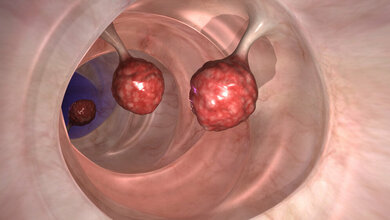

Darmkrebs ist laut Krebsgesellschaft bei beiden Geschlechtern die dritthäufigste Krebserkrankung. In Deutschland erkranken jährlich rund 33.000 Männer und 28.000 Frauen an Darmkrebs. Ab dem 50. Lebensjahr tritt diese Krebserkrankung vermehrt auf. Das mittlere Erkrankungsalter liegt bei Anfang bzw. Mitte 70 Jahren. Vor allem in fortgeschrittenen Krankheitsstadien stützt sich die Behandlung noch weitestgehend auf die traditionelle Chemotherapie. Eine neue Generation von Krebstherapien, die so genannten Immuntherapien, waren nur bei einer kleinen Untergruppe von Darmkrebsarten wirksam. Forscher der TU Dresden unter der Leitung von Prof. Sebastian Zeißig haben nun im Mausmodell Proteine identifiziert, die vielversprechende Ziele für neue Immuntherapien gegen Darmkrebs darstellen könnten. Ihre Ergebnisse unterstreichen auch die zentrale Rolle von Darmbakterien bei der Entstehung der Krankheit.

Forscher analysierten Darmkrebsproben und suchten nach Proteinen, die in den Tumorzellen, nicht aber im gesunden Gewebe vorkommen. Zwei Proteine weckten ihr Interesse. B7H3 und B7H4 waren in großer Zahl in Darmkrebszellen vorhanden, während sie im gesunden Gewebe fast nicht nachweisbar waren.

„Wir beschlossen, B7H3 und B7H4 in Darmkrebszellen zu blockieren“, sagt Dr. Peuker. „Das Ergebnis war verblüffend. Tumorgewebe, in dem diese Signale ausgeschaltet waren, wuchs deutlich langsamer oder schrumpfte sogar. Wir konnten beobachten, dass die Immunzellen nun in das Krebsgewebe eindringen konnten und begannen, die Tumorzellen zu kontrollieren.“ Weitere Tests bestätigten, dass die Proteine B7H3 und B7H4 tatsächlich als Checkpoint-Proteine funktionieren. „Durch die Blockierung dieser Signale konnte das Immunsystem plötzlich Tumorzellen angreifen“, fügt Prof. Zeißig hinzu.

Proteine auch in den Metastasen zu finden

Das Team stellte fest, dass B7H3 und B7H4 nicht nur in den primären Darmkrebstumoren, sondern auch in den Metastasen in der Leber vorhanden waren. Das Ausschalten dieser Proteine verlangsamte das Wachstum der Primärtumore, aber auch der Lebermetastasen. Sie beobachteten, dass einige der behandelten Mäuse trotz ihrer metastasierenden Tumore langfristig überlebten.